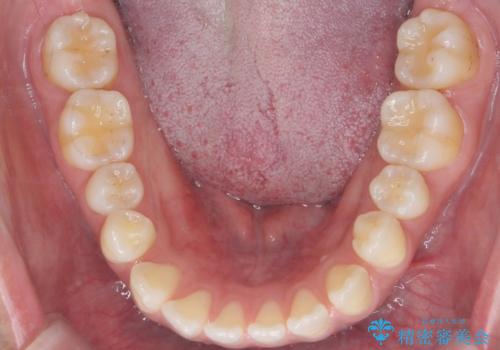

下の前歯を後方に移動するため、ゴムを上下のマウスピースにかけてもらいました。